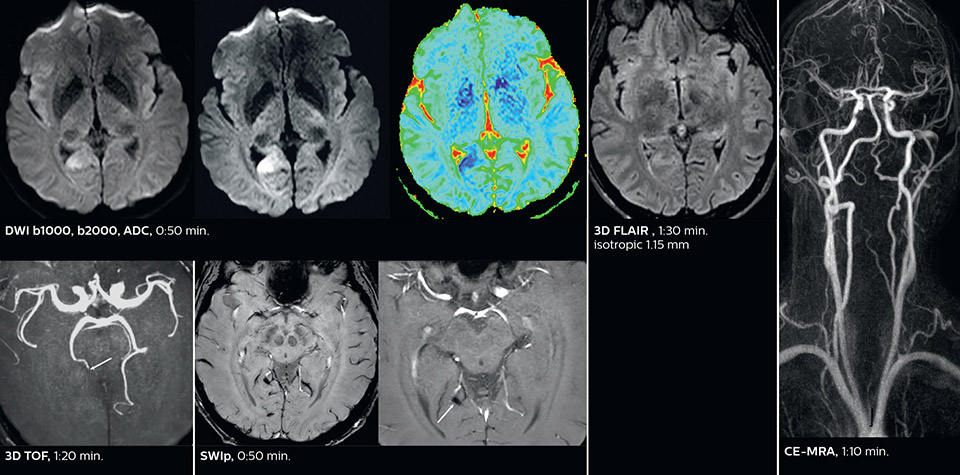

Comprehensive stroke MRI within acceptable time

Dr. Savatovsky appreciates the improvements and flexibility that Elition with Compressed SENSE and MultiBand SENSE provides, particularly for stroke patients. “For stroke, it allows us to cut about 5 minutes off of our stroke protocol, or to keep the same acquisition time and get more insights.” The ability to perform more sequences can help in making a swift and confident diagnosis. “For example, our stroke cases usually include the regular sequences that every center does (b1000 diffusion, FLAIR, time-of-flight angiography), but we also image supra aortic vessels, and we can replace a gradient echo sequence with a fast 50-second susceptibility-weighted sequence, and all of this doesn’t add much time. because all the regular sequences are accelerated on Elition.” “The time savings with Compressed SENSE and MultiBand SENSE make it easier to add sequences to give us additional insights. Depending on the context and the first results, we might add a DSC perfusion to assess the ischemic penumbra, an ASL perfusion to help find an alternative cause in case of normal diffusion, or add a high-resolution T1 sequence for a stroke patient, to quickly assess wall imaging in emergency cases. The additional sequences can help improve patient management, because we can already consider some alternative diagnoses if the morphological MRI is normal.”

Improved diffusion imaging in stroke patients

Using MultiBand SENSE allowed the staff to improve their diffusion quality. “Our diffusion sequence was already fast before, about 40 seconds. Now with Elition, it still lasts 40 seconds, but we improved the spatial resolution by 0.2 mm and use high b-values to be more sensitive to visualize changes related to acute stroke,” says Dr. Savatovsky. “We now also developed a high resolution DTI sequence (1.3 x 1.3 x 2 mm) that can be reformatted and takes 2 to 5 minutes depending on the coverage. We use it every time we have a doubt, or when we expect the diffusion to be abnormal but don’t see that on the fast sequence. We occasionally spot small ischemic infarctions that would not have been visible with the regular diffusion sequence.”

This is an example of acute ischemic stroke with distal occlusion of the right posterior cerebral artery. Note the improved visibility of the ischemic territory on the diffusion weighted image with high b-value. The 3D FLAIR shows a distal PCA occlusion. The fast SWIp depicts the thrombus on the isolated second echo image. The total scan time (including SmartBrain, preparations and a fast 3D T1w TSE Gd) is 8:00 minutes.